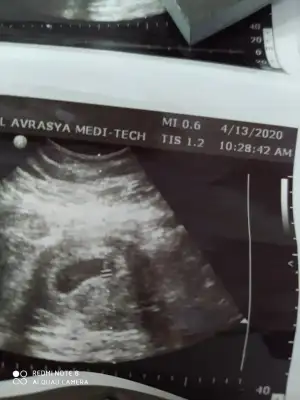

dr soylemeden siz gorun genital nub teorisi ( bebegin cinsiyeti)

Kızlar benim nub teorisi tuttu kızım olacak inşallah 🤗 Bu ara isim arayışındayız isim önerileriniz varsa alırım valla 😍

Doktorumun söylediği bir tüyomda var cinsiyet tahmini ile ilgili. Varsa daha keseyi gördüğünüz zaman ki ultrasonlarınız yardımcı olurum😘

Merhaba banada yardımcı olurmusunuz lütfen nubu görünmedi belki keseden belli olur